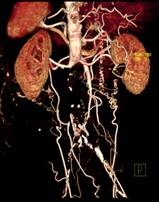

※肝脏、胰腺、肾脏CT-DSA 及灌注功能一站式检查

脑血管畸形CTA ,大血管成像:动态容积成像实现大范围动态血管检查